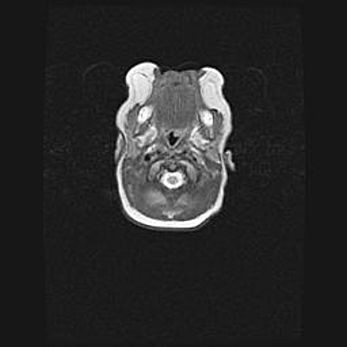

Церебральная ишемия II.

Возраст: 5 дней

Вес: 3400 г

Пол: женский

Окружность головы: 35 см

Срок гестации: 39 недель

Церебральная ишемия – это заболевание, характеризующееся недостаточностью (гипоксией) либо полным прекращением (аноксией) снабжения мозга кислородом по причине закупорки одного или нескольких сосудов. Это приводит к  что метаболическим расстройствам различной степени тяжести в тканях головного мозга, развитию коагуляционных некрозов и гибели нейронов.